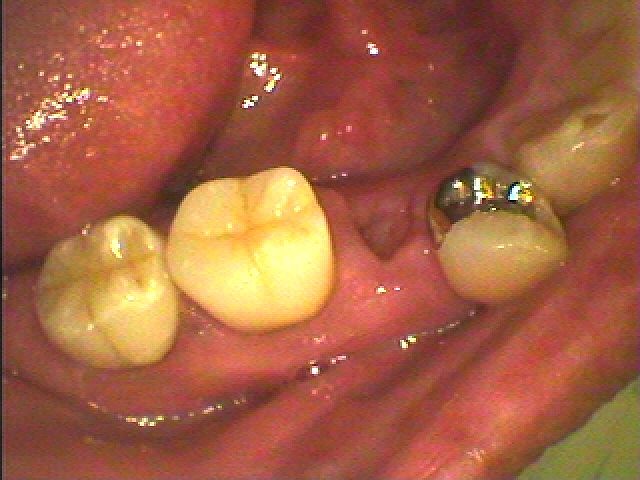

ブログ一覧|広島市安佐南区の歯科医院 ブログ一覧 トップ ブログ一覧 お知らせ スタッフブログ ブログ一覧 2017/11/25 7を抜歯しインプラントに置き換えました。 2017/11/25 コアから脱離してきました。 弱い歯だったので破折が原因でした。 2017/11/25 もともと悪い7番だっつたのですが、矯正にてアンカーとして使っていました。 2017/11/25 保険治療でもこんなにきれいには治ります。 2017/11/25 咬合再構成。 乱れた噛み合せをもう一度もつようにつなげていきます。 2017/11/25 インプラントを支台としたジルコニアクラウンになります。 この中の2本がインプラントになります。 2017/11/25 完成後口腔内に入ったところになります。 2017/11/25 これよりシンタリングに入ります。 << 1 2 3 4 5 … 824 825 826 827 828 … 870 871 872 873 874 >> Web診療予約 初めての方へ 選ばれ続ける理由 院内設備について 歯が痛いしみる一般歯科 歯がぐらぐらする歯周病 健康な歯を保ちたい予防歯科 子供の虫歯予防をしたい小児歯科 銀歯をセラミックに審美歯科 白い歯を目指しませんか?ホワイトニング 矯正専門医がいるので安心矯正歯科 抜けた歯を補いたいインプラント・入れ歯 医院案内 スタッフ紹介 メリィハウス歯科クリニックオフィシャルホームページ ラベンダー歯科クリニックオフィシャルホームページ お知らせ・ブログ ホーム 診療科目 一般歯科 歯周病治療 予防治療 小児歯科 審美治療 ホワイトニング 矯正歯科 入れ歯・インプラント マウスピース矯正 初めての方へ 院長・スタッフ 設備紹介 医院案内・アクセス メニューを閉じる